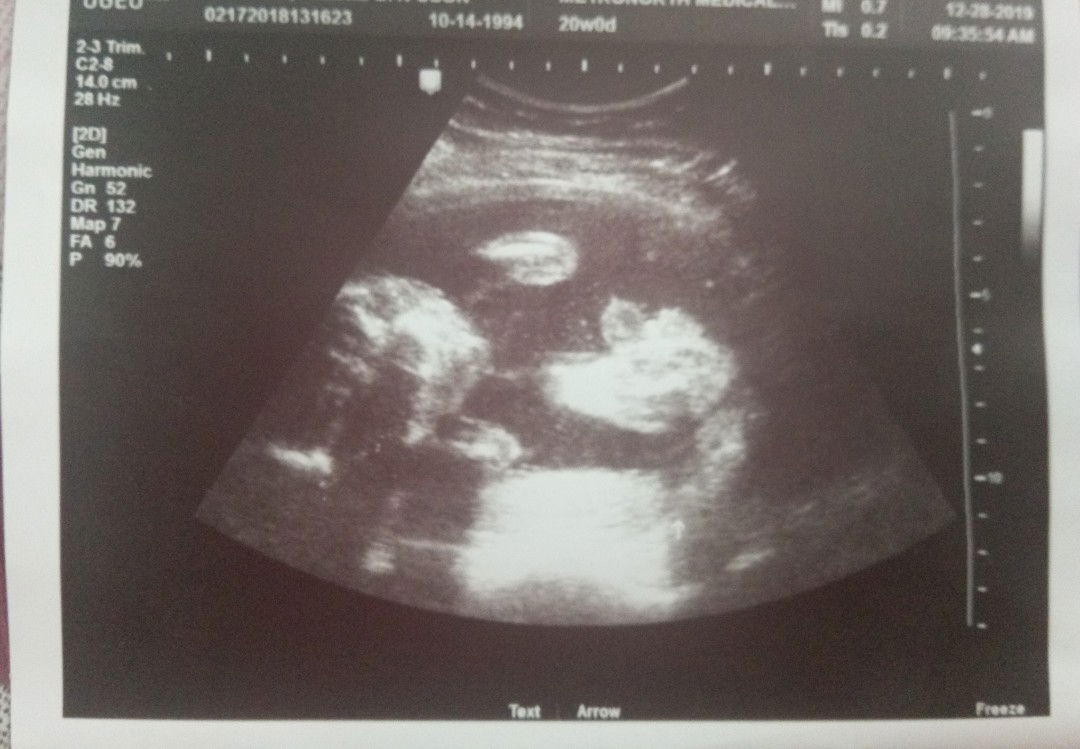

20 weeks and 5 days Baby Boy

Share ko lang po. Napaaga po ang pag ultrasound sakin kasi po na ospital ako dahil sa sobrang pain. Dpat 22 week sya para mkita gender ni baby pero 20 weeks palan nakita na baby boy sya. Sobrang sarap sa feeling na mkita mo si baby kahit sa ultrasound lan. Tapos sobrang kulit pa nya panay hikab . Gusto ko lang mashare kasi super happy ako ???